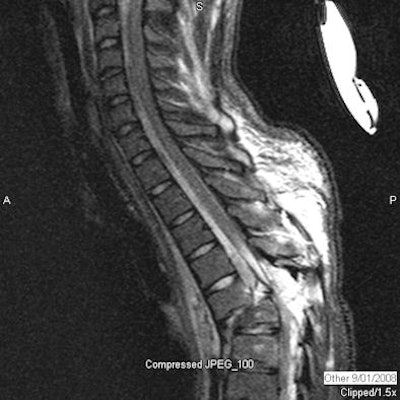

Twenty-one children had spinal fractures, and five children had spinal cord injuries.

| Spinal cord injury: Sagittal CT (above) and short-tau inversion recovery (STIR) MRI (below) images of the thoracic spine of a 16-year-old male who was found in a ditch by a passerby after a rollover ATV accident. He suffered compression fractures of T5 and T6 with anterior subluxation of T5 over T6 with intraspinal fracture fragments and severe spinal cord injury. Spinal cord showed near complete transaction at this level. Subsequently, he developed dural cerebrospinal fluid leak at T5-6 level. He also suffered fracture of C2 vertebra and multiple facial bone fractures. He was not wearing a helmet. On a recent follow-up eight months after the injury, there is no improvement in paraplegia. All images courtesy of Dr. Chetan Shah. |